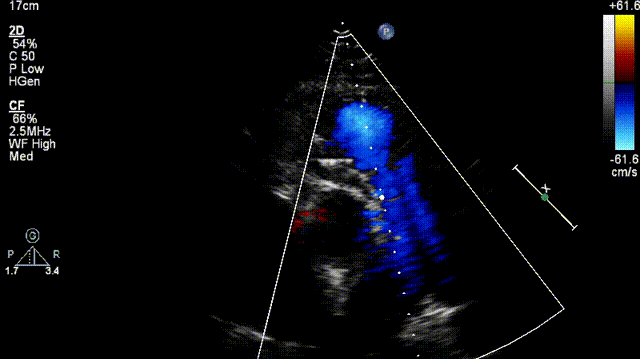

术前造影显示肺动脉瓣大量舒张期逆向血流。

术前造影显示肺动脉瓣大量反流

患者全麻状态下,经右侧股静脉入路将加硬导丝置入右肺动脉,建立通路,沿导丝将介入肺动脉瓣PT-Valve®推送至肺动脉主干,通过造影准确定位后逐步释放瓣膜。再次行肺动脉造影显示瓣膜支架位置良好,瓣叶工作正常,未见明显肺动脉瓣反流和瓣周漏。

术后造影显示无肺动脉反流(左图,肺动脉远端造影;右图,肺动脉近端造影)